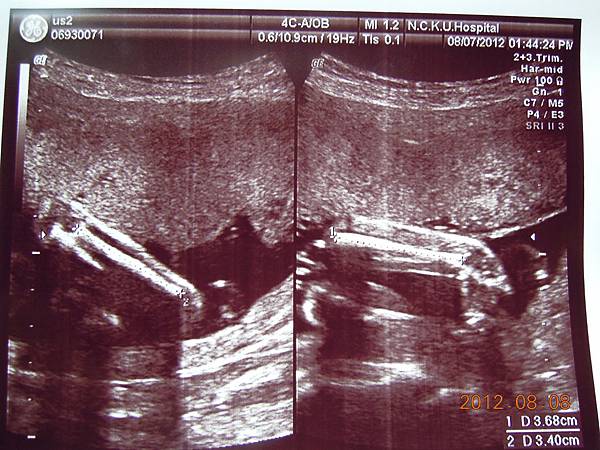

女醫師看起來超熟練,一邊照還會邊跟我解釋,這是逼逼的大腿,小腿,心臟,腎臟.....等等器官,一邊跟我媽聊天,說他生幾個....

除了比較明顯的骨頭可以看的出來,其實我們看不太懂,但是他精熟的技術很快把每個部位的大小都量測出來,我躺在床上看著上頭的螢幕,慢慢欣賞他的每張超音波照片~~

接下來就是他的一堆檢查照片啦~~